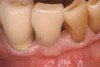

Figure 2  The extraction socket was grafted with a mixture of pure-phase β-TCP and heme from the surgical site.

Figure 2

Thirty patients were selected on the basis of need for dental extractions with bone preservation and/or augmentation in the socket before the placement of a dental implant. These patients were cleared medically for oral surgical procedures. Preoperative clinical photographs and periapical radiographs were taken. After administration of local anesthesia, full-thickness labial and lingual/palatal flaps were elevated. Minimal soft-tissue manipulation was performed to allow visualization of the entire alveolar crests and debridement of fenestrations and/or dehiscence defects, if present. Elevation of each tooth or retained roots was performed, using periotomes, luxatomes, proximators, root forceps, and any other instruments and procedures as required to extract the tooth with minimal trauma (Figure 1). After extraction and thorough debridement of the socket by mechanical means, clinical photographs were taken. The sites then were grafted with a resorbable β-TCP of small particle size, 150 µm to 500 µm (Cerasorb) (Figure 2). This material has been used and reported in the literature for almost 30 years as a viable bone graft in orthopedic and other surgical specialties. In this study, the granules of β-TCP were mixed thoroughly with blood from the surgical sites and the sockets filled to ideal contours faciolingually and apicocoronally. The grafts and adjacent 3 mm of alveolar bone then were covered with resorbable collagen barriers (BioMend®, www.zimmerdental.com) (Figure 3). The flaps were repositioned and the areas closed with an appropriate number and type of sutures. No attempts were made to obtain primary closure over the exposed barriers. Postoperative radiographs and clinical photographs were taken. Subsequently, sutures were removed at 1 to 2 weeks.